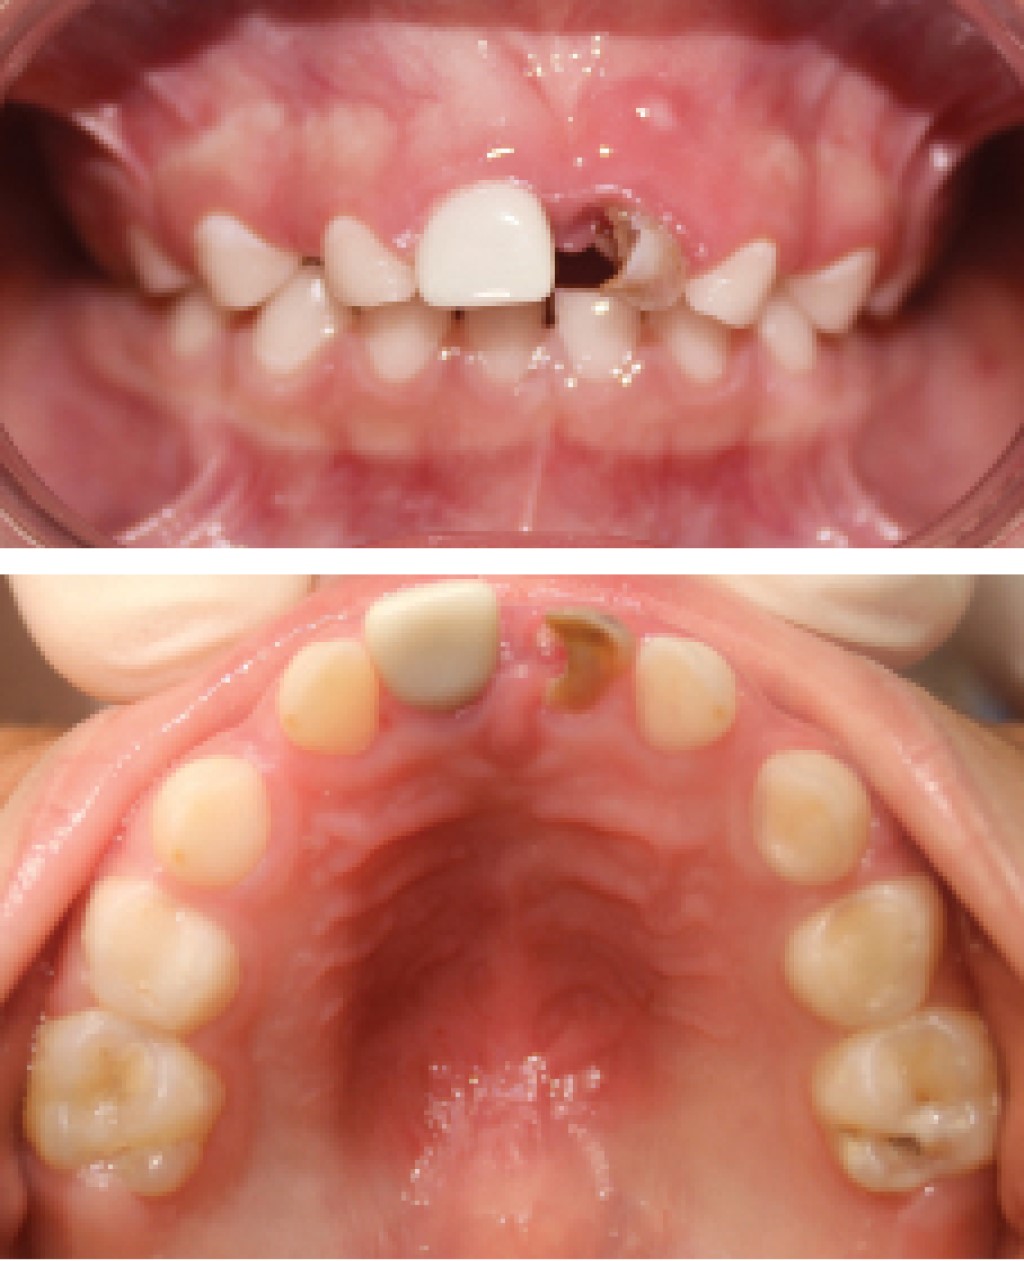

Al realizar exploración clínica, se observa dentición primaria completa de acuerdo con la edad. Tejidos blandos se encuentran sin alteraciones. En el sector anterosuperior se diagnosticó caries de la infancia temprana al observar clínicamente lesiones blancas no cavitadas, presencia de restauración con corona de zirconia NuSmile en el órgano dental (OD) 51 y en el OD 61 se observa lesión cariosa severa asintomática, con aparente antecedente de trauma debido a sus características físicas como discromía, movilidad y pérdida de estructura coronal, así como remanente de absceso localizado en la zona superior de la gingiva (Figura 1).

Figura 1